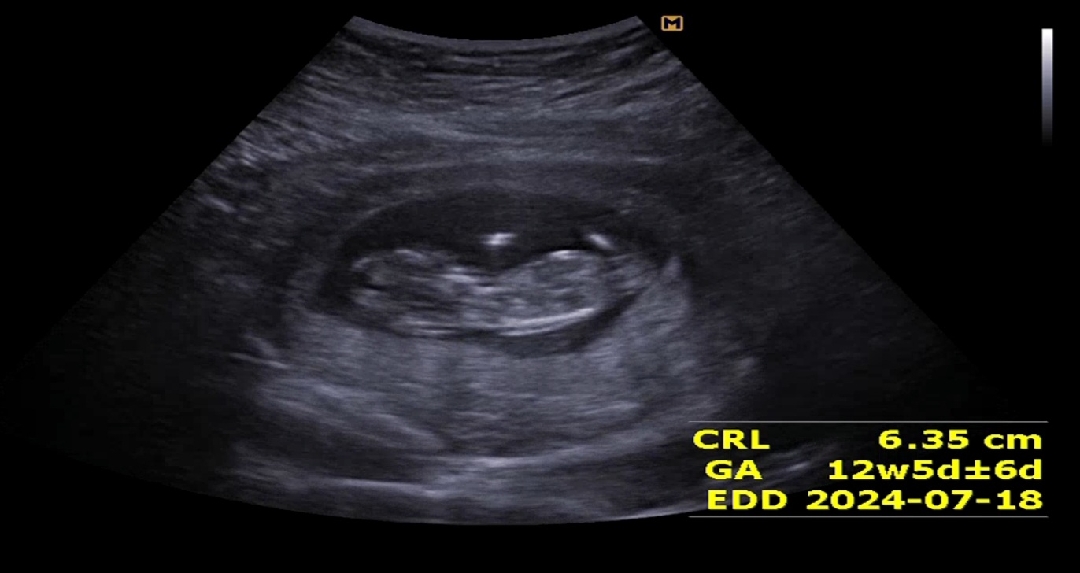

8주.. 병원다녀온 이틀 후부터 여태 아프다가 12주엔 잠 못 잘 정도로 배가 너무 아파서 ㅠㅠ 정기검진 예약보다 며칠 일찍 내원했는데, 온 김에 정밀 보자고 하셔서 보고 왔어용 감기도 걸렸었고 계속 컨디션 메롱이어서 오히려 살이 4kg 빠졌거든욬ㅋㅋㅋㅋ ㅠㅠ 애기는 예정일보다 며칠 더 훌쩍 커서 너~무 다행이었지만 양수가 적어서 ㅠㅠ 애가 껴 있다고, 옆모습 지금은 의미없겠다고 단호박 멘트 듣고 다 내려놨어요 저 같은 산모도 있으니 괘념치마세오,, 성별은 4주 후에 만나요 땅땅,,,ㅋㅋㅋㅋ ㅠㅠ